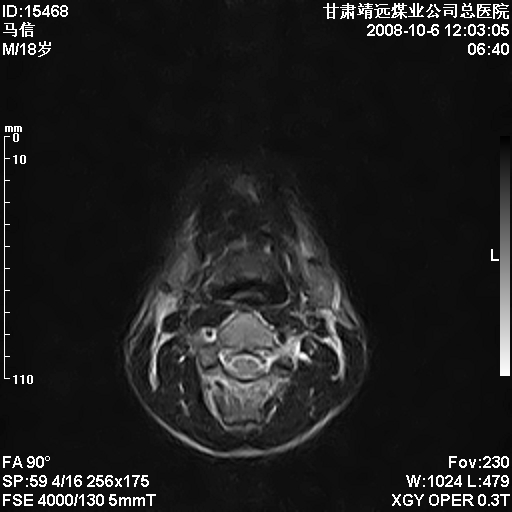

患者18岁,学生,在玩耍中受伤来检查,患者喜欢打篮球。颈椎内异常信号影,我们考虑占位,但是不像占位,又考虑硬膜囊的增厚,大家关建看颈椎椎管内的那个异常占位信号

脑脊液流动伪影?

是正常的脑脊液波动伪影

脑脊液流动伪影

你说的占位是伪影。在我们医院1.5t和3.0t的mr上是经常看见的。